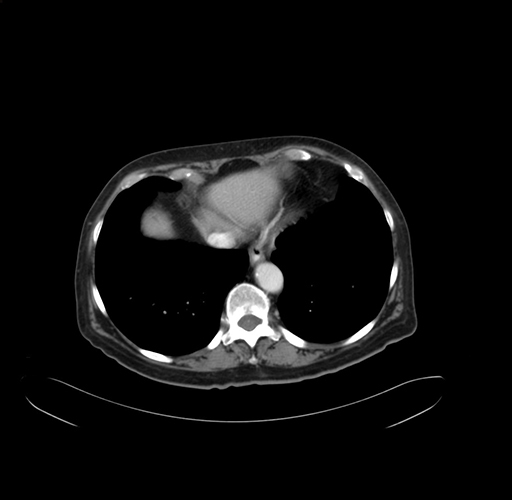

Pre-Chemo: Axial Venous